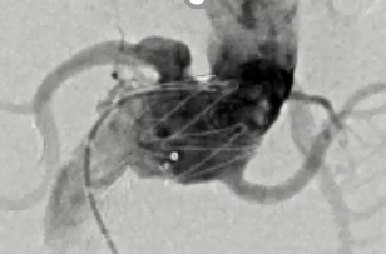

大动脉炎

男性,15岁

发现血压增高五年,双下肢乏力伴麻木一年余

最高血压达180/110mmHg。四年前行右肾动脉支架成形术,一年前复查时发现再狭窄,我院超声、CTA等相关检查提示“多发性大动脉炎”。

大动脉炎,主动脉及其主要分支广泛受累,多发节段性狭窄

右侧肾动脉近段支架置入,支架内腔稍变窄,右肾灌注尚可显影良好

左肾萎缩

手术方案:

腹主动脉-双侧髂动脉人工血管旁路术+右肾自体移植术

右肾移植于右髂窝,肾动脉与右髂内动脉吻合

术后5天复查CT

术后1年

术后3年